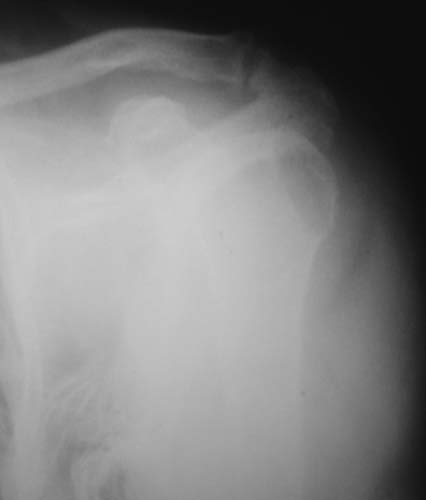

Активное отведение 80 гр., при пальпации - головка плечевой кости безболезненно вправляется и тут же самостоятельно вывихивается. Наложена косыночная иммобилизация, рентгенография (r3) и МРТ.В нашем диагностическом центре МРТ исследование плечевого сустава выполнено впервые, опыта у нас маловато :(.Вопросы: уточнение диагноза? какие исследования провести? тактика лечения?

К сожалению, нет! Сейчас попробую еще раз переснять снимки и МРТ. Возможно получится более качественно. Тем более, что упомянутый участок явно виден в прямой проекции рентгенограммы.

"Прицельная" съемка малопонятного очага.

Вопрос доктору Цориеву (для улучшения дальнейшей работы:) ).

1. На рентгене - нижний подвывих плеча и очаг остеолиза суставного бугорка с четкими контурами (вдавленный перелом на фоне остеопороза ? доброкачественная опухоль? аваскулярный некроз ? (хотя ни разу не слышал об аваскулярном некрозе плеча..)

Судя по снимкам, речь идTт о типичном случае Hill-Sachs Lesion. По этому поводу я позволю себе некоторый экскурс:

97 % всех вывихов плеча происходит по механизму комбинации отведения, разгибания и наружной ротации (А. Гринспан). В момент вывиха головка плеча ударяет о нижний край гленоида, что ведет к вдавленному или компрессионному перелому одной или обеих структур. Чаще всего, однако, повреждение возникает в задней латеральной области головки плечевой кости на переходе от головки к шейке. Этот диагноз можно выставить на основании рентгеновского снимка в переднезадней проекции с внутренней ротацией плеча. Несколько реже видно повреждение гленоида о передненижний перелом края. То, что мы называем Bankart Lesion. Это повреждение видно на ре. снимке в п.з. проекции при нейтральной позиции плеча. Разумеется хрящевые и мягкотканные повреждения (в смысле Банкарт) мы увидим лучше всего на ЯМР.